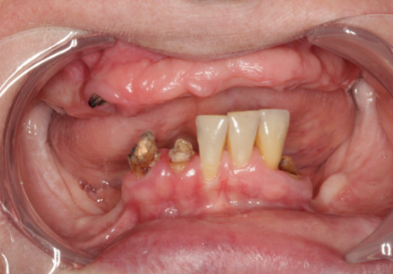

임플란트를 찾고 계신가요? 치아가 상실되면 가능한 빨리 임플란트 치료를 받으셔야 합니다.

치아를 상실된 채 그대로 두게 되면 치아 배열에 불균형과 턱뼈 손실, 잇몸질환 문제가 발생합니다.

특히, 치아가 빠진 자리에 턱뼈가 충분한 자극을 받지 못하면, 뼈가 약해지면서 얼굴 외형의 변화까지 생기게 됩니다.

이렇게 상실된 치아로 인해 외관상 좋지 않은 변형과 턱 관절 장애까지 유발하게 되면 더이상 되돌릴 수 없는 단계에 이르게 됩니다.